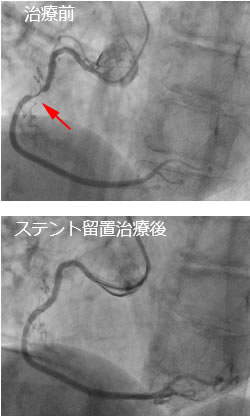

カテーテルを用いた冠動脈治療を冠動脈形成術PCIと言います。冠動脈形成術PCIで現在最も主流なのがステント留置術です。

治療手順は、まず冠状動脈の狭窄部にガイドワイヤー(細い針金のようなもの)を通過させ、それに沿って先端に風船のついたバルーンカテーテルを狭窄部まで挿入し、風船を拡張します。こうすることで狭窄の原因となっていたコレステロールの塊を圧排し、冠状動脈の血管内腔を拡張します。次に、あらかじめステント(金属の網)の載ったバルーンカテーテルを狭窄部まで挿入し、バルーンを用いてステントを拡張し冠状動脈内に留置します。場合によっては、再狭窄が起こりにくくなる薬剤溶出性ステントを使用します。

治療前

ステント留置治療後